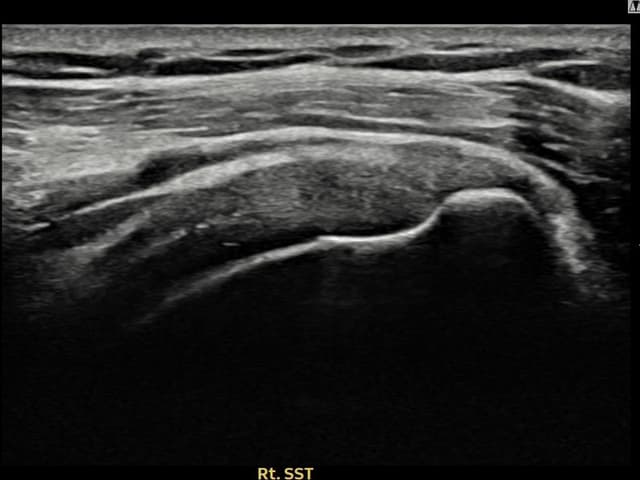

実際の患者様の施術前後の超音波画像。

手術なしで実現できる回復をご確認ください。

[経過期間: 23.09.01~23.11.03]

[縫縮術] 超音波検査にて右 棘上筋腱 滑液包面側部分断裂(8mm × 4mm (腱厚の約35%欠損))を確認。縫縮術施行後、腱の連続性が回復し、日常生活に復帰されました。